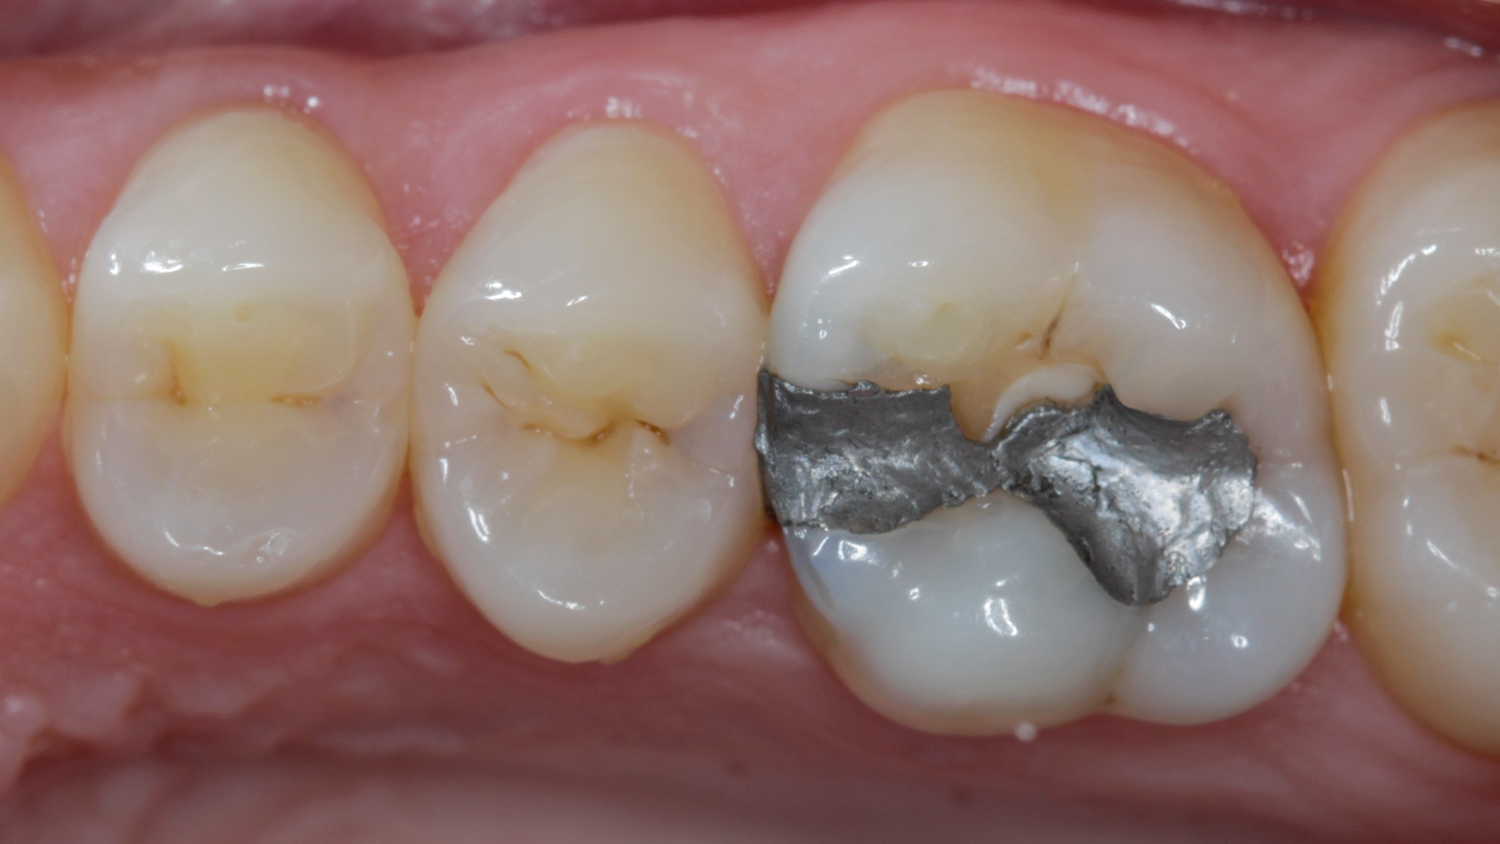

Case: Initial case showing defective and fractured old amalgam restoration.